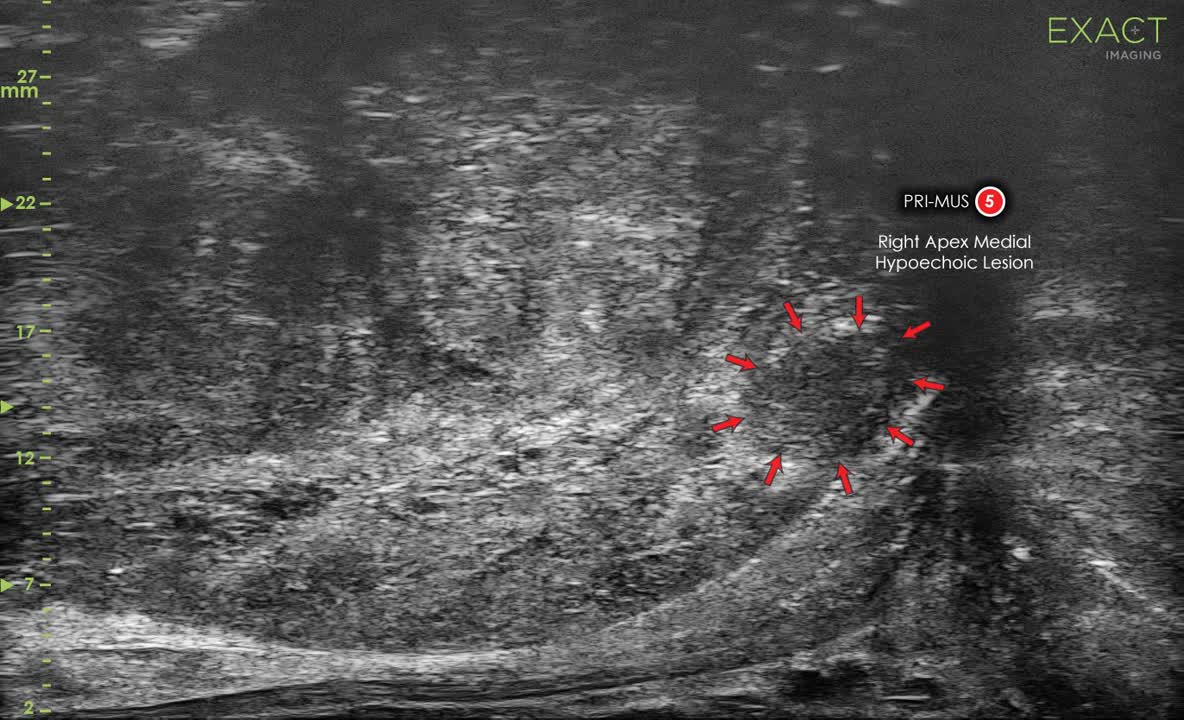

Exact Imaging was founded to streamline prostate cancer detection, biopsy, and management in a cost and time effective fashion, building on the same micro-ultrasound imaging principles our lab is investigating. This FDA and CE approved scanner is now entering the North American and European markets. There are currently about 175 installations of Exact-Vu at leading urology clinics around the world. Dozens of Clinical Trials are ongoing and, in particular a large multi-centre international randomized controlled trial called OPTIMUM is running to establish level 1 clinical evidence. We are investigating additional applications of the ExactVu technology, such as photoacoustic imaging.